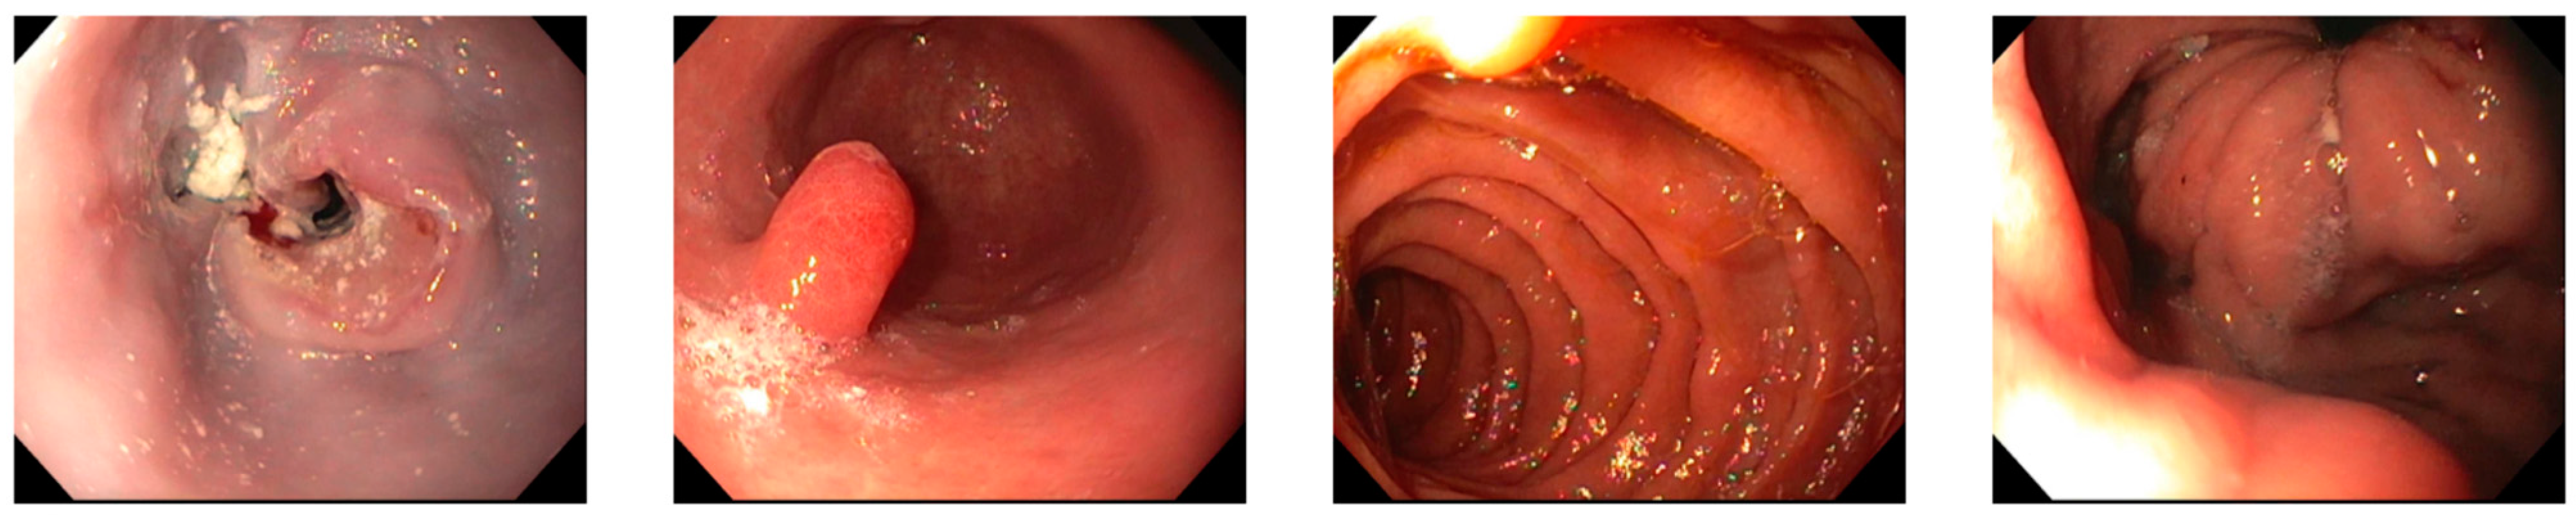

2. Case Presentation